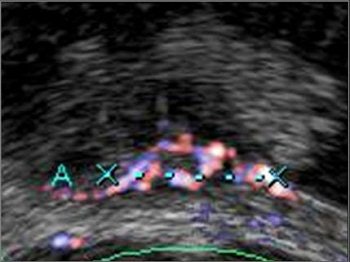

Freehand scanning was used for 3D data acquisition, and surface rendering and multiplanar reconstruction for 3D data analysis. Power Doppler ultrasound was used to differentiate the extent of infiltration. The criteria for staging were based on the vascularity of the tumor's basement. The gold standard was the histomorphology results.

| Power Doppler ultrasound criteria for staging vascularity of the tumor basement. Above, submucosal vessels; second, half muscle wall vascular. Below, whole muscle wall vascular; second image, few vessels in the perivesical walls; third image, massive flow in the perivesical fat. Images courtesy of Dr. Veronika Gazhonova, Russian President Medical Center and Russian State Medical University. |